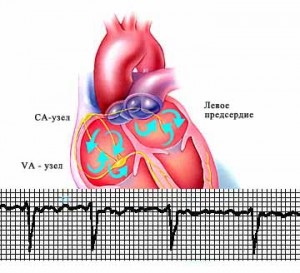

Egy másik fontos pont automatikus összehúzódása a szív fektetjük a sejtek, amelyek képesek generálni spontán, hanem elrendelte idegi impulzusok. Ezek a szerkezetek ismertek, mint a szív vezetési rendszer. Ezek bemutatva klaszterek idegsejtek módosított a csomópontok és az ideg kötegek kinyúló tőlük. Itt van, hogy vannak olyan impulzusok, amelyek később okozhat összehúzódása a szívizom ugyanazon a frekvencián. A legerősebb közülük - a szinusz csomó. Ez létrehoz egy gerjesztési, hogy a szokásos körülmények között gátolják az ilyen folyamatok más szerkezetek a vezetési rendszer. Emiatt nevezik a fő pacemaker. Ez a következő elvek létre pacemaker a szív pitvarfibrilláció.

Pitvarfibrilláció utal egyik típusú abnormális tachycardiák. A fő mechanizmus annak előfordulása a megjelenése ektópiás (további) tűzhely, amely létrehozza idegimpulzusok nagyfrekvenciás (120-220 / min.) Eloszlási karakterisztikáját legtöbbjük csak pitvarokat. Kamrák ugyanakkor csökkenteni lehet a normál vagy megnövelt mértékben. Ez attól függ, hogy a szilárdsági tulajdonságokat és a méhen kívüli helyszínen a természetes pacemaker (sinus csomó.) Ha olyan erős, hogy versenyez a bázis, hogy része áthalad impulzusok a kamrákba, gyakoriságának növelése a fájások. Ilyen helyzet áll elő, amelyben a pitvarok, mintha remegés nem teljesítő teljes darabok.

Összhang a szív, melyet egy speciális szív ingerületvezetési rendszer. Ezek speciális sejtek termelnek és elektromos impulzus vezető irányítja összehangolt összehúzódása a szívizom.

Impulzus, amely kiváltja összehúzódása a szív keletkezik a jobb pitvarba, az úgynevezett sinus csomópont (a pacemaker). Ez az egység felelős a tény, hogy a szív dobog frekvenciája 60-90 ütés percenként. Aztán jelet ad a többi pitvarok, így azok vágni, majd a kamrákba.

Zavarok ebben a rendszerben, és ok szívritmuszavarok (aritmiák).